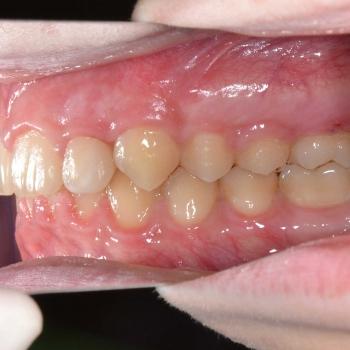

Balázs és édesanyja konzultáció céljából keresett fel, hogy egyértelműen kiderüljön számukra szükséges-e a fogszabályozó kezelés vagy sem. Már rögtön az első vizsgálat alkalmával fény derült több olyan problémára is, melyek fogszabályozást igényelnek. Ilyen volt például a súlyos mélyharapás, a hátrafelé dőlő felső metszők, illetve az Angle II. osztályú harapási eltérés is. A mintavétel, a röntgenek és a fotók kiértékelése után további problémaként merült fel a felső fogív szűkülete és a kismetszők méretaránytalansága, azaz a túlzott keskenységük.

A kezelést Quadhelix fogszabályozóval kezdtük el a felső fogív tágítása érdekében. Ezután került felragasztásra az alsó és felső fogívre a Balázs és szülei által kiválasztott fém önligírozó fogszabályozó. Ezen túlmenően Bite turbo harapásemelő segített a mélyharapás, intermaxillaris gumihúzás pedig az Angle II. osztályú harapási eltérés korrigálásában. A fogak méretaránytalansága miatt a kezelés végén a kismetszőket tömőanyaggal építettük fel, hogy a tökéletes harapáshoz résmentes fogazat társuljon. A fogak felépítéséhez az adott fogakat nem kell megfúrni, a tömőanyag kizárólag ragasztásos módszerrel rögzül, így nem károsodik a fogzománc.